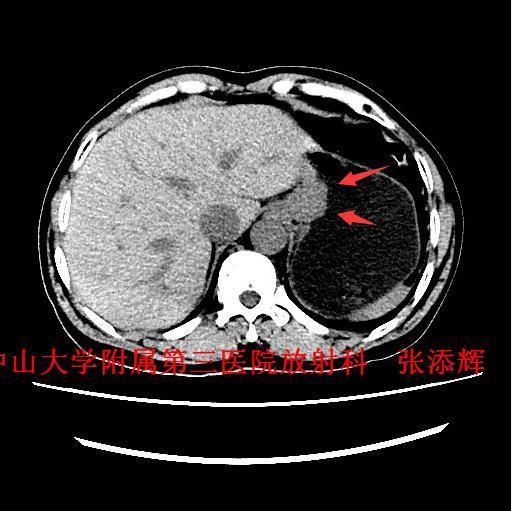

主诉:反复吞咽不畅2月余 病史:患者反复吞咽不畅2月余,吞咽固体、质硬食物时明显,伴恶心、呕吐少量食物,呕吐多在进食半小时内发生。无呕血、咯血、黑便,体重下降约4Kg。

查体:全身浅表淋巴结未触及肿大。腹平软,无压痛、反跳痛。 辅查:1、胃镜:贲门Ca?;2、上腹部CT示:贲门胃底癌,浸润胃壁全层,小网膜囊多发稍大淋巴结。

诊断:贲门癌 治疗:排除手术禁忌征后,全麻下行“腹腔镜下根治性全胃切除术”。术中及术后病理诊断为“中-低分化腺癌,浸润胃壁全层,1/61枚淋巴结转移,分期T3NIM0,ⅡB期”。